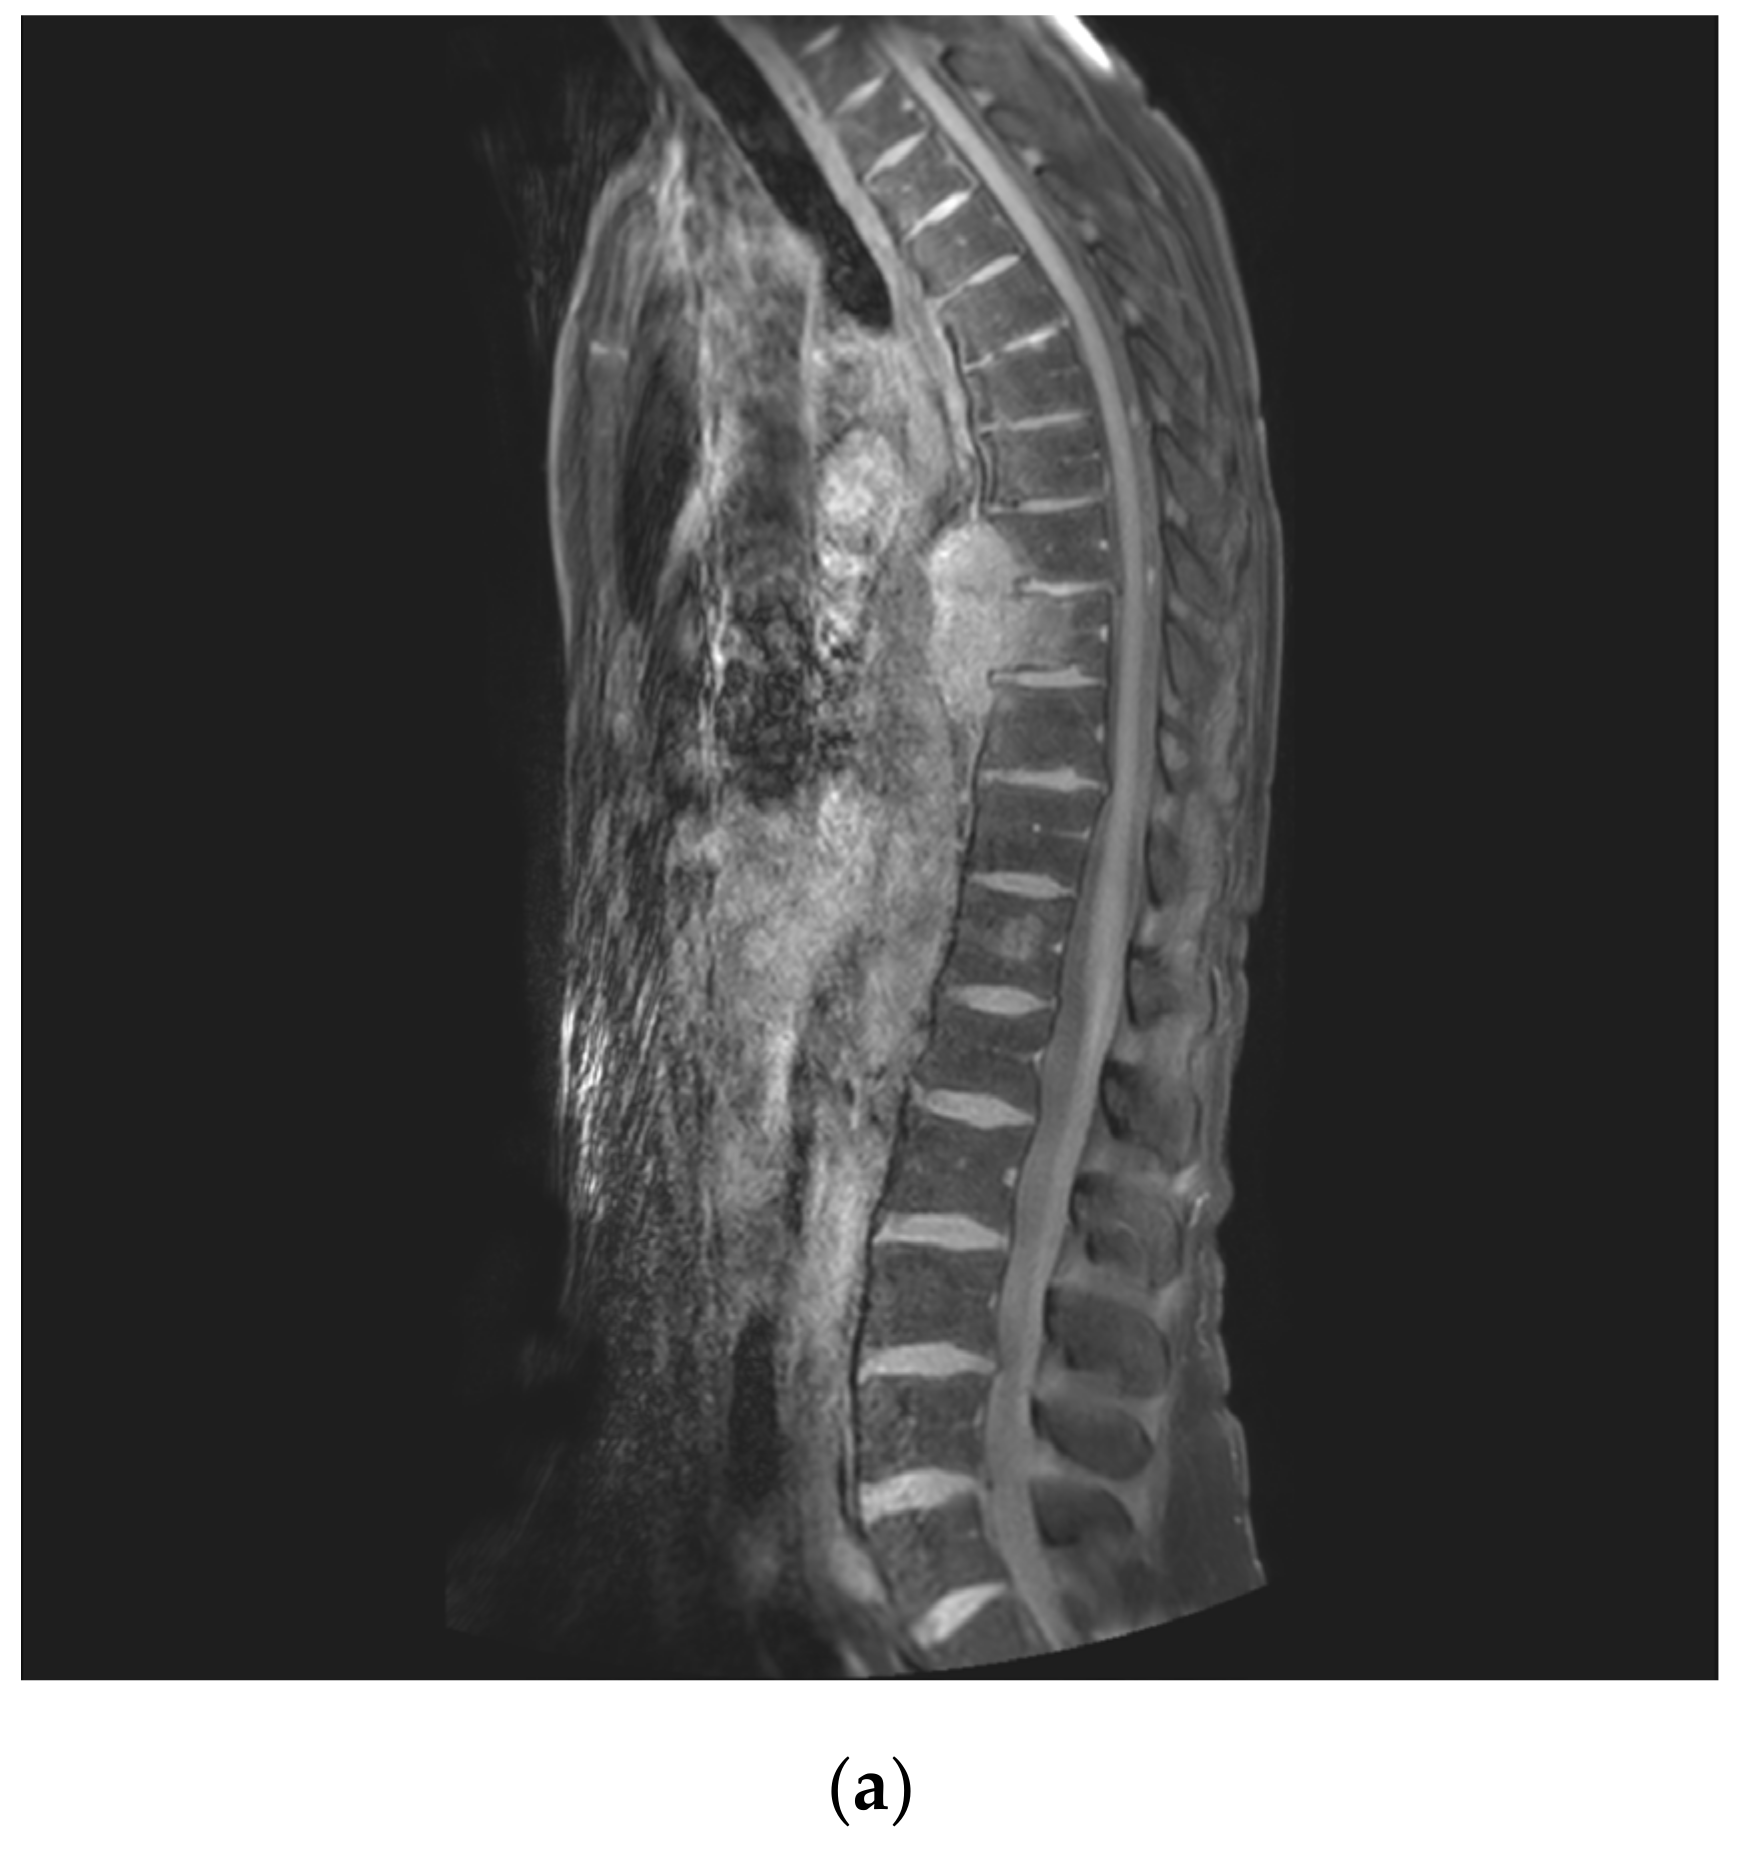

2.2. Imaging Studies

2.3. Surgical Planning